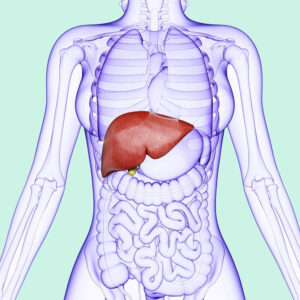

These are being an excellent book on normal home remedies for very common diseases to chronic diseases. It suggests remedies for ailments from head to toe – simple, easy-to-use, and effective.